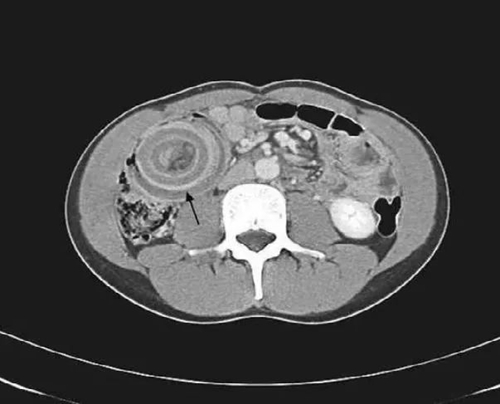

接診醫(yī)生根據(jù)孩子病史、癥狀和體征,考慮腸套疊可能性大,于是給患兒做了超聲,超聲橫斷面上呈“大環(huán)套小環(huán)”的征象。醫(yī)生立即給孩子進(jìn)行空氣灌腸復(fù)位,治療很成功。隨后,童童被收治入院,進(jìn)行進(jìn)一步治療。經(jīng)過(guò)及時(shí)對(duì)癥治療,目前孩子順利康復(fù)出院。